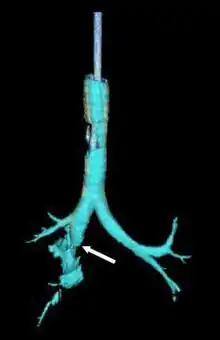

Reconstruction of the trachea and bronchi with x-ray computed tomography showing disruption of the right main bronchus with abnormal lucency (arrow)[1]